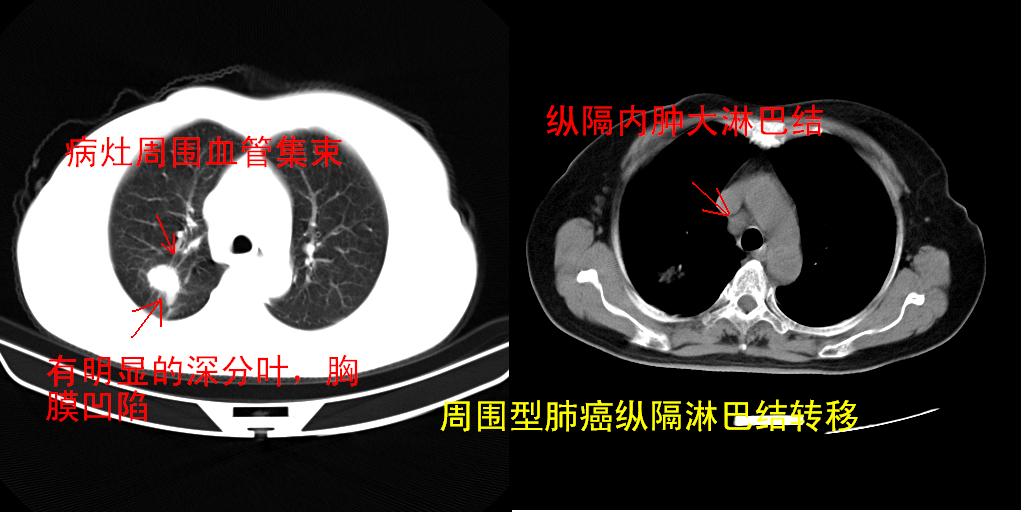

以下是引用zjzjr在2007-3-23 13:28:00的发言:[br]右肺上叶后段可见一结节状高密度影,可见毛刺征,胸膜凹陷征及血管导入征,纵隔内可见肿大淋巴结影.考虑右肺上叶周围型肺癌伴纵隔淋巴结转移.

以下是引用zjzjr在2007-3-23 13:28:00的发言:[br]右肺上叶后段可见一结节状高密度影,可见毛刺征,胸膜凹陷征及血管导入征,气管前腔静脉后可见肿大淋巴结影.考虑右肺上叶周围型肺癌伴纵隔淋巴结转移.